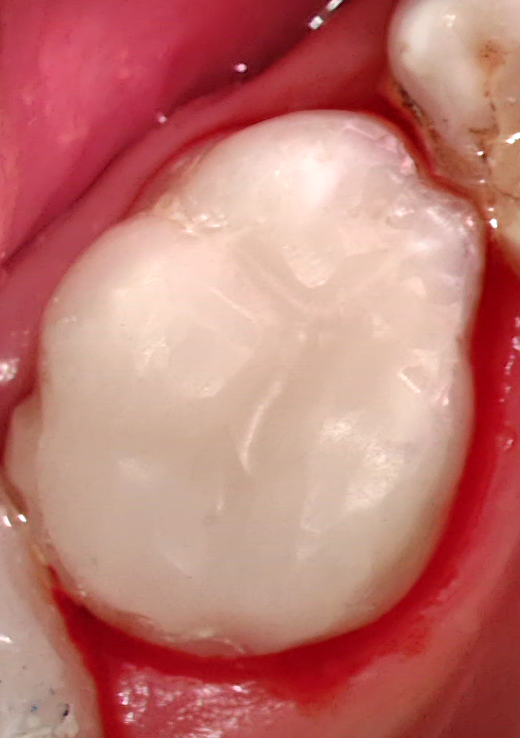

Gyökértömés

Végső tömés/ Pótlás